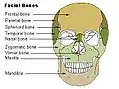

Ossos faciais

Ossos faciais -

Crânio visto de frente

Crânio visto de frente -